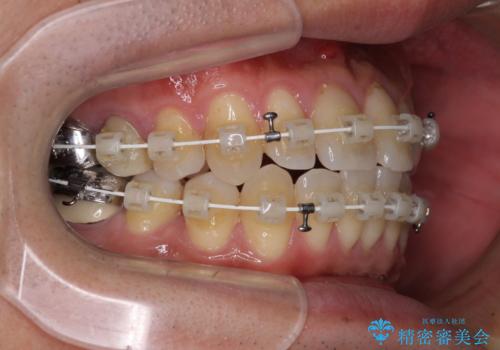

- 審美装置

- 治療期間

- 1年2ヶ月

ワイヤー矯正でもマウスピース矯正でも対応可能とお伝えし、非常に悩まれていましたが、2年後に転勤の可能性が高いとのことで、治療終了までの期間を想定しやすいワイヤー矯正にて治療を行うこととしました。

前歯のクロスバイトは、改善の途中で歯髄壊死を起こすリスクが高くなるため、マウスピース矯正よりもワイヤー矯正をお勧めしております。